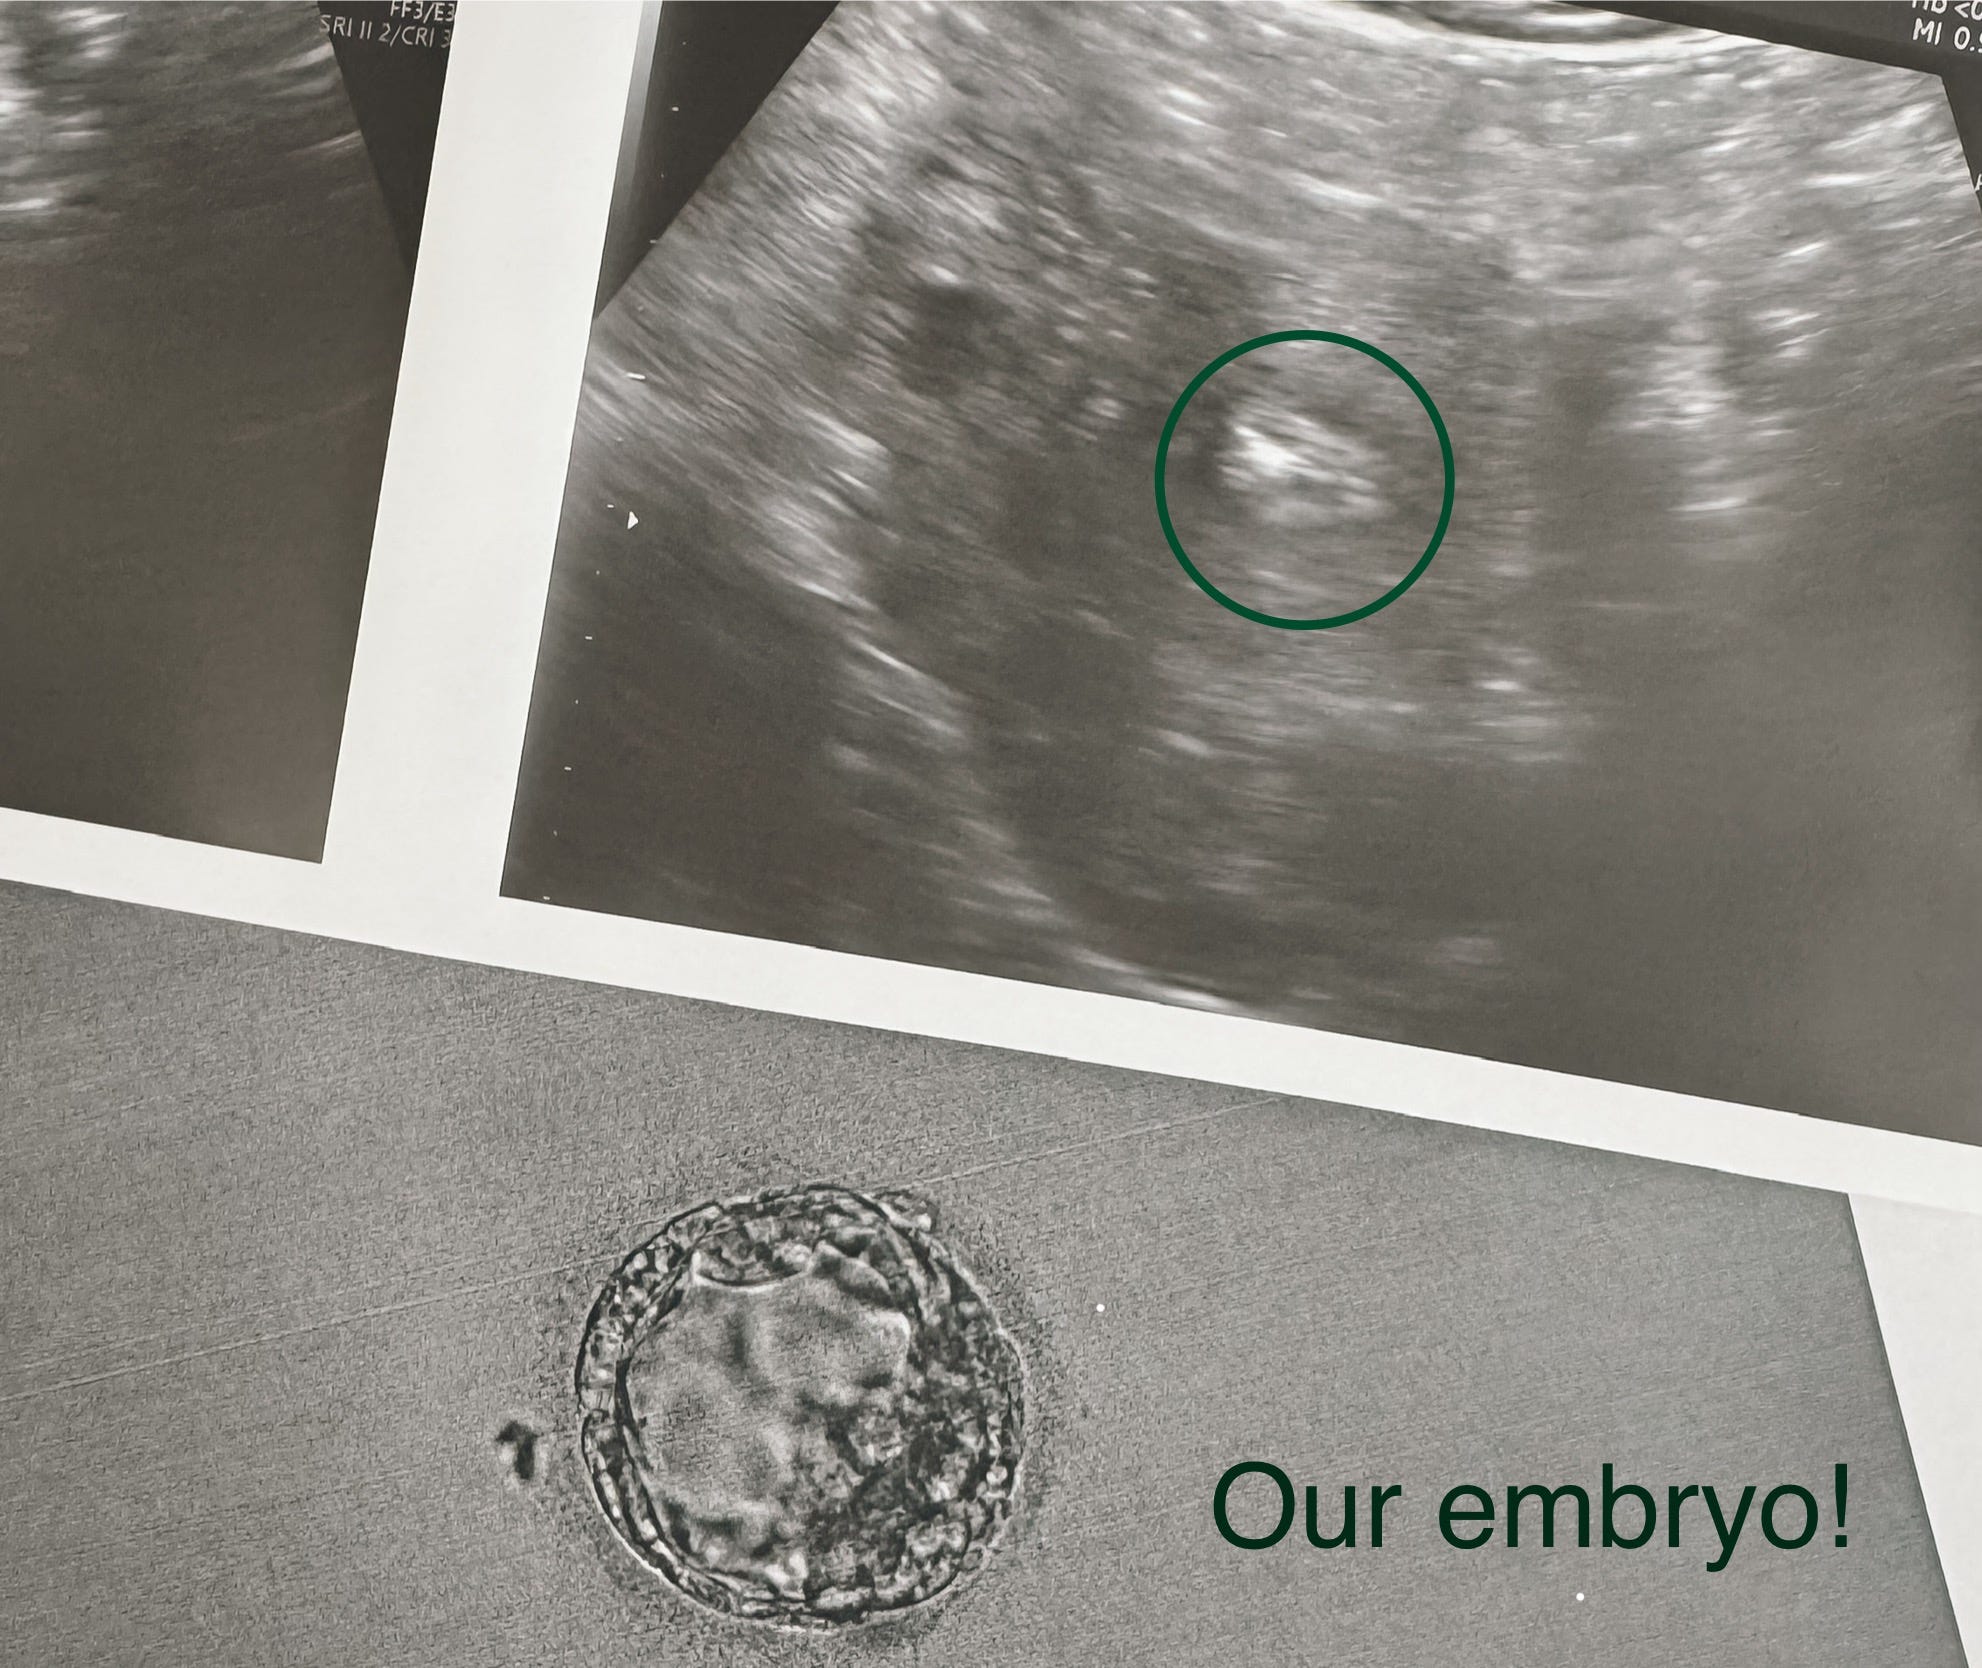

It’s Wednesday, November 5th, 2025, and I’m doing a frozen embryo transfer. Somehow, someone in a secret lair mixed my scrambled eggs and Michael’s slow swimmers to create a one-week-old embryo. Now, they’re putting it into my uterus and praying that “it sticks.” I’ll know if I’m pregnant in two weeks.

It still feels odd doing IVF. Just last year, I jokingly told my friend I’d never “buy a baby”, and now I’m filing that statement into a cabinet labeled “The Most Insensitive and Idiotic Things I’ve Ever Said.” Because, as they slide our sweet little embryo into place, things aren’t just shifting inside my body; they’re shifting inside my head, too.

Last year, I horridly and playfully mocked IVF; this year, I’m sprawled across a sterilized bed, praying that God intervenes and science succeeds where my body has not.